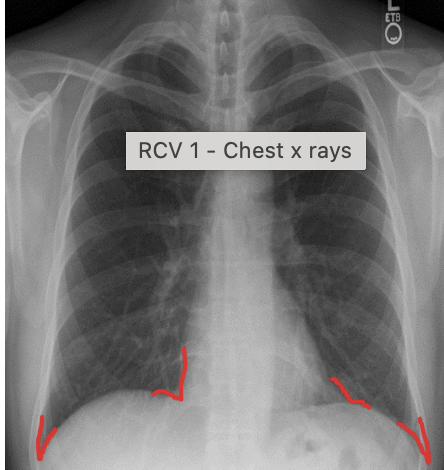

how to check the diaphragm on chest xray?

-check the position of the R & L semi-diaphragm, the right should be higher than the left due to the liver

-also should be a nice dome shape

-check for any flattening - can be seen in hyper inflated lungs as seen in COPD

-check cardio phrenic and cost phrenic angles on diaphragm